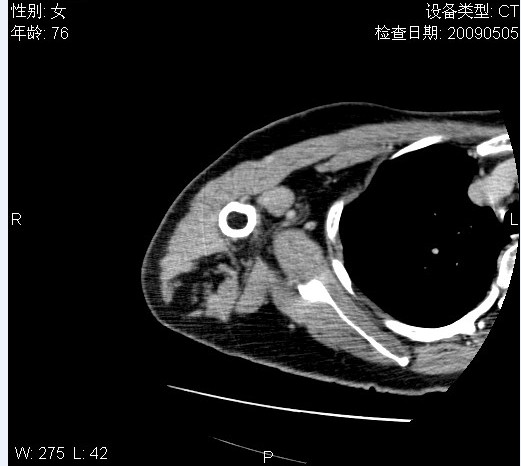

标题: CT19811:女,76岁,右上臂肿物1个月 [打印本页]

标题: CT19811:女,76岁,右上臂肿物1个月

使用了造影剂,可惜效果不太好

右肱骨上段软组织内见梭形低密度影,边界清楚,最长径约54mm.

病理结果:脂肪瘤。术中见肱骨骨膜受侵,有出血,量不详。

当时诊断意见:右肩三角肌内蔓状血管瘤(先天性动静脉瘘)。

本人对病理结果有个疑问:单纯的脂肪瘤内为什么有条状软组织影,那应该脂肪肉瘤才对啊?

该病例增强效果欠佳,由于经验欠缺,我们注射对比剂是由下肢足背静脉给药。注速2.0。虽然如此,但我们可以看到肿块内部条状软组织影是强化的,而且是连续的,并可见供血动脉是由腋动脉的其中一支即肩胛下动脉分出。从这些征象我们可以得出诊断:蔓状务血管瘤。

可病理偏偏为脂肪瘤,我怀疑取材有问题。因为蔓状血管瘤异常扩张的静脉外周是脂肪成分,它可以侵犯肌组织及骨骼。当取材于外周,那当然是脂肪瘤。此时我认为临床的最终诊断不应单从病理出发,应该综合考虑。